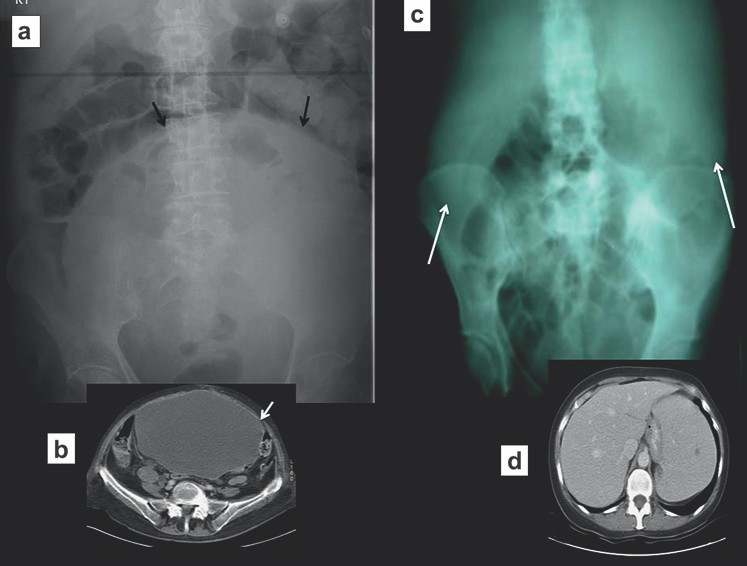

Các phim X quang thường quy thường cho thấy các quai đại tràng giãn. Manh tràng có mức giãn lớn nhất, khi đường kính ngang gần đến 80 mm thì có nguy cơ cao bị thủng (Hình 3). Một cân nhắc quan trọng là liệu ruột non có giãn không. Nếu không có khí ở ruột non, có nghĩa là van hồi-manh tràng đóng kín và làm tăng nguy cơ thủng đại tràng.

Hình 3. Tắc đại tràng (a) Phim X quang bụng cho thấy đại tràng giãn to. Lưu ý manh tràng giãn rất to. (b) Chụp CT cho thấy đại tràng giãn có vị trí chuyển tiếp ở khung chậu do u ác tính (UTBM) của đại tràng sigma gây tắc.

Xoắn xảy ra khi đại tràng sigma xoắn mạc treo của nó gây tắc ruột quai đóng (closed loop obstruction). Các bệnh nhân có thể có các triệu chứng đau bụng cấp hoặc âm ỉ tùy thuộc vào tình trạng xoắn gây tắc hoàn toàn hoặc bán phần. Trên phim X quang bụng, quai đại tràng sigma giãn to (không còn ngấn ngang) nhô lên khỏi tiểu khung và kéo cao đến phần trên của ổ bụng, thường lệch sang phải. Hình ảnh này được gọi là dấu hiệu “hạt cà phê” (Hình 4).

Hình 4. Xoắn đại tràng sigma (a) Phim X quang bụng thấy đại tràng sigma giãn to nhô từ tiểu khung lên ổ bụng (hình “hạt cà phê”) sát với đại tràng ngang. (b, c) Chụp CT xác định xoắn đại tràng sigma. Lưu ý dấu hiệu “mỏ chim” của mạc treo đại tràng sigma bị xoắn.

Xoắn manh tràng

Xoắn manh tràng ít xảy ra so với xoắn đại tràng sigma, chỉ chiếm dưới 5% các trường hợp tắc đại tràng. Xoắn thường ở những người trung niên, điển hình là những người không có tiền sử phẫu thuật ổ bụng. Xoắn ở đại tràng lên, vị trí điển hình là ngay trên van hồi-manh tràng. Phim X quang bụng thường cho phép chẩn đoán và cho thấy quai ruột giãn to kéo từ hố chậu phải đến góc phần tư trên trái ổ bụng. Ruột non thường giãn và đại tràng ở đầu xa bị xẹp. Chụp cắt lớp vi tính hiếm khi được yêu cầu để khẳng định chẩn đoán, nhưng mục đích để phát hiện mạc treo bị xoắn và đoạn ruột bị thiếu máu hoặc thủng (Hình 5).

Hình 5. Xoắn manh tràng (a) Phim X quang bụng đứng thấy một quai ruột giãn nhô vào góc trên trái ổ bụng. Lưu y không có khí trong các đoạn đại tràng, các quai ruột non giãn to (b, c) Chụp CT xác định xoắn manh tràng, cũng thấy hình “mỏ chim” của mạc treo manh tràng xoắn.